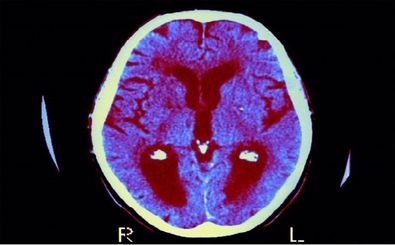

دانشمندان یک سامانه «هوش مصنوعی» را توسعه دادهاند که با استفاده از اسکنهای MRI متوالی، امکان بازگشت تومور مغزی در…

دانشمندان موفق به توسعه یک رویکرد درمانی جدید برای درمان تومورهای مغزی در کودکان شدند.